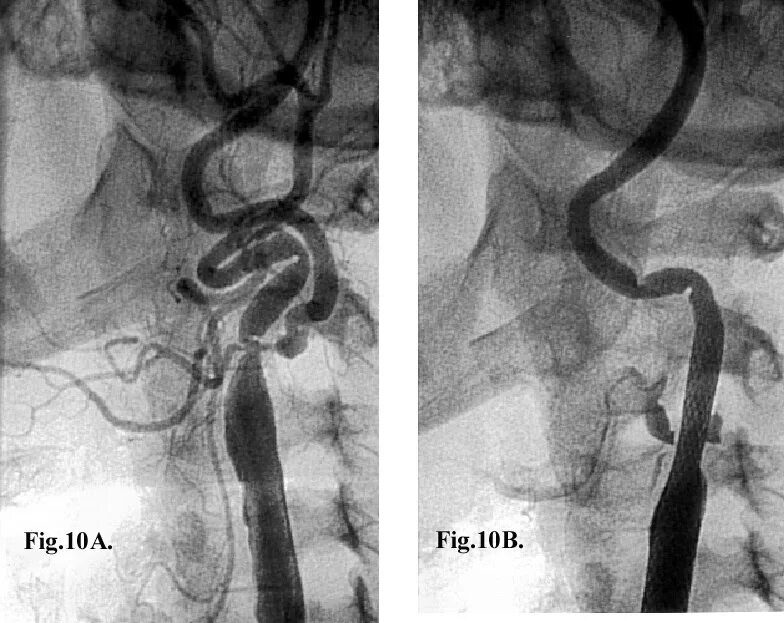

С образная извитость артерий